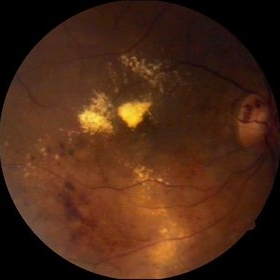

Age-Related Macular Degeneration

Sep 10 2014 by Mehul A Shah

65-year-old female presented with sudden loss of vision.

Photographer: Drashti Netralaya, Dahod

Imaging device: FF 450

Condition/keywords: age-related macular degeneration (AMD)